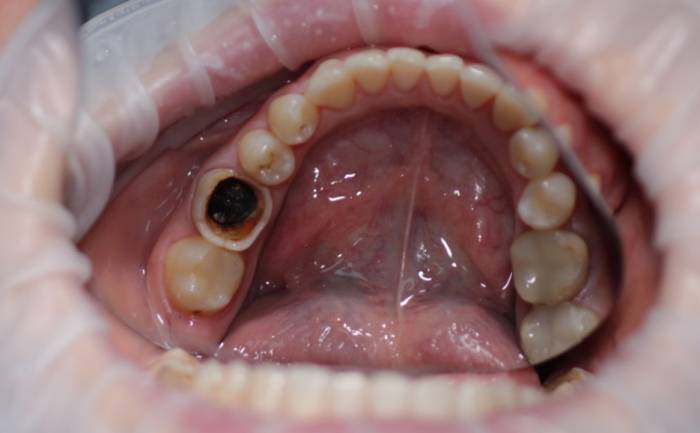

- Неверный диагноз может привести к частичному лечению. Если зуб болит после установки пломбы и под ней обнаруживается чернота, это может указывать на неполноценное лечение, например, скрытый периодонтит.